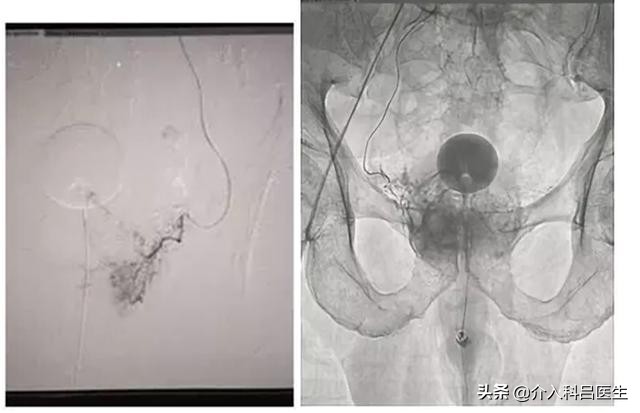

经导管动脉栓塞术是局麻下采用股动脉穿刺,将导管送入前列腺的供血动脉,造影后,注入颗粒性栓塞剂,造成前列腺组织缺血坏死,最终前列腺体积缩小,尿路压迫缓解。

优点:前列腺动脉栓塞术与经典的经尿道激光切除相比,疗效相当,但并发症少,而且为微创手段,出血少、感染机会少,且为局麻手术,危险性更小,住院时间缩短,甚至可以当天出院。在性功能方面,也会得到理想的效果。